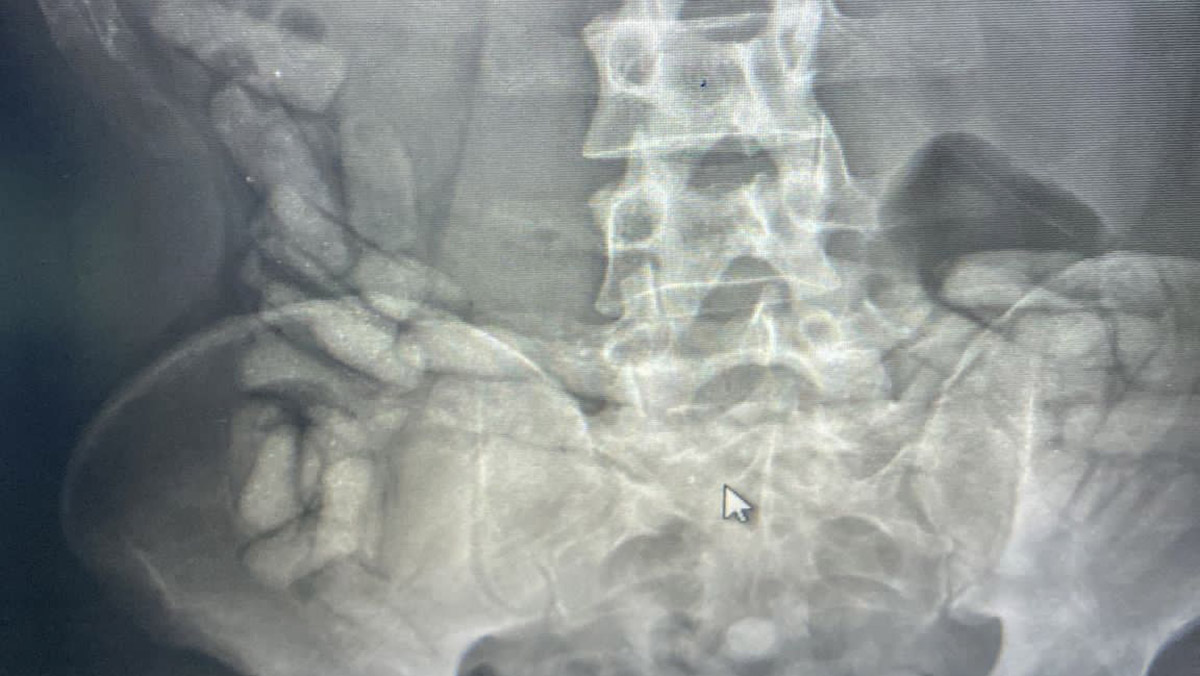

İl Emniyet Müdürlüğü Narkotik Suçlarla Mücadele Şube Müdürlüğü ekipleri, Doğubayazıt ilçe merkezi girişinde İran uyruklu R.R. ve A.G.’yi durdurup, üzerlerini aradı. Aramada, şüphelilerden R.R.’nin ayakkabısının içerisine zulalanmış 2 paket halinde 522,40 gram metamfetamin ele geçirildi. Bunun üzerine 2 şüpheli gözaltına alındı. Durumundan şüphelenilen A.G., mahkeme kararıyla muayene için Doğubayazıt Devlet Hastanesi’ne götürüldü. A.G.’nin röntgen çekiminde bağırsaklarında yabancı madde tespit edildi. A.G.’nin doğal yollarda çıkardığı maddenin 55 kapsül halinde 432 gram Afyon sakızı olduğu belirlendi.